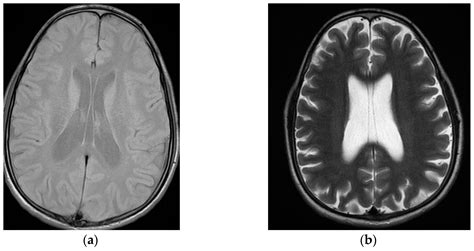

Diagnosing abnormalities in the Cavum Veli Interpositi typically involves the use of advanced imaging techniques. Magnetic Resonance Imaging (MRI) is the most commonly used method for visualizing the Cavum Veli Interpositi and other structures within the brain. MRI provides high-resolution images that allow clinicians to assess the size, shape, and position of the Cavum Veli Interpositi, as well as any potential abnormalities.

• cavum veli interpositi mri